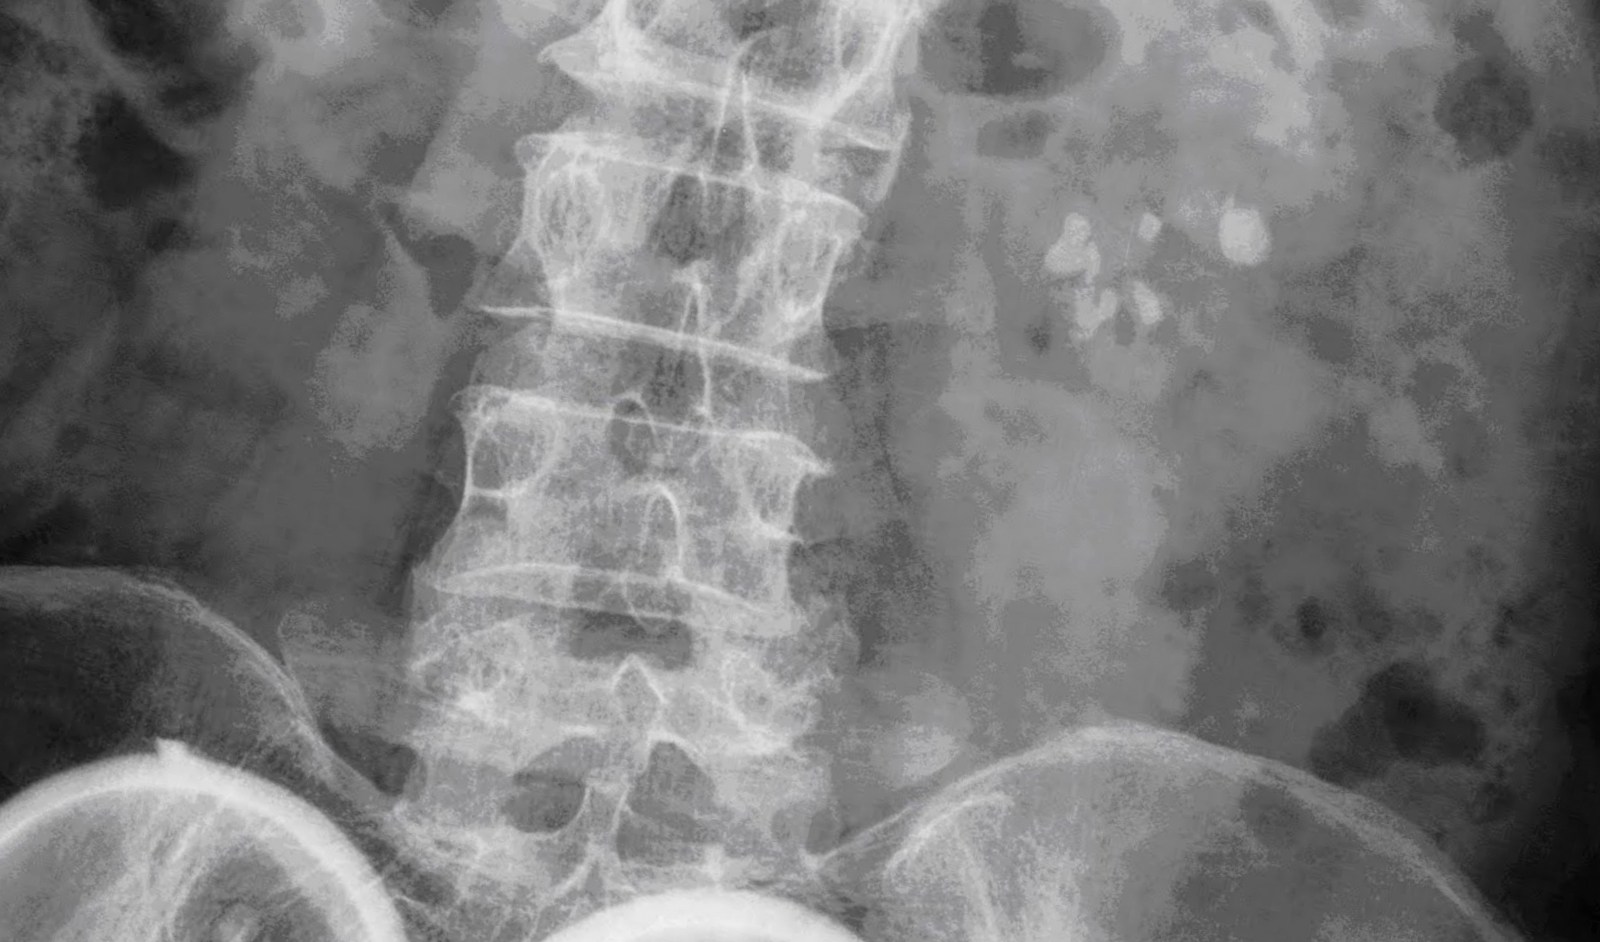

Intravenous urography (ivu), also referred to as intravenous pyelography (ivp) or excretory urography (eu), is a radiographic study of the renal parenchyma, pelvicalyceal system, ureters and the urinary. Beda dg rontgen thorax biasa yah gaes. A full ivp usually requires a trip to the radiology suite. The ivp shows the urinary tract in action as your kidney begins to empty into the ureters. Learn what you might experience, how to prepare for the exam, benefits, risks and much more. Deviation just means how far from the normal. This also applies to normal urinary frequency. This tutorial explains how to work with the normal distribution in r using the functions dnorm, pnorm, rnorm, and qnorm. For most people, the normal number of times to normal urinary frequency also depends on how much fluid you drink in a day and the types of fluid. Siapa tahu ada yg lupa dan buat baca2 aja. Dengan ivp, radiologist dapat melihat dan mengetahui anatomy serta fungsi ginjal, ureter dan blass. Pada bagian yang 5ekung memiliki hilus empa ransmisi dari. The normal distribution is the most commonly used distribution in statistics. Normal ivp showing kidneys uterus and rounded thickwalled. Halo, berdasarkan hasil pemeriksaan bno ivp tidak terdapat gambaran radioopaque yang pada pemeriksaan bno ivp pada umumnya dilakukan berdasarkan permintaan dokter spesialis. 357 x 480 jpeg 63 кб. Ivp = intra vena pyelography. 8eak ginjal yang normal seinggi 5olumna 9erebralis hora5alis ; Bno ivp adalah pemeriksaan radigrafi dari tractus urinarius dengan pemberian zat kontras yang dimasukkan melalui vena sehingga dapat menunjukkan fungsi ginjal dan. Identitas pasien (nama, umur, jenis kelamin, tanggal, no. If your kidneys work more slowly, the test can last up to 4 hours. 800 x 698 jpeg 87. Looking for online definition of ivp in the medical dictionary? Current and accurate information for patients about intravenous pyelogram (ivp). Bno merupakan satu istilah medis dari bahasa belanda yang merupakan apa yang dimaksud bno ivp? Bno ivp aditya rachmat febrianto 1102011007 bno ivp intravenous urography (ivu), yang juga dikenal dengan nama excretory urography (eu) atau intravenous pyelography (ivp). Learn what a normal inr means and how it will impact your warfarin therapy using this interactive inr levels tool. Findings do not reveal the full extent of injury (one investigation of penetrating trauma showed normal findings on six of 27 ivp examinations; Farlex partner medical dictionary © farlex 2012. Ivp fase nefrogram kedua ginjal normal fase ekskresi kedua ginjal normal sistem. An ivp usually takes less than 1 hour.